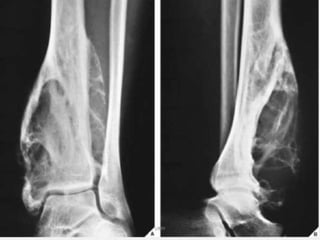

- Radiographic features : metaphysis of immature

skeleton ,

DIGNOSTIC- well marginated , centrally located ,purely

lytic lesion.

radiolucent that expand and thin the cortex .

FALLEN FRAGMENT SIGN - # fragment in the cyst

DD :ABC & fibrous dysplasia

FALLEN

FRAGMENT SIGN

UMY

Bone cyst of

humerus

Pathologic fracture

“Falling Fragment Sign”

- Cysts progressfrom active to quiescent to involutional UMY - stage . cysts usually shrink as patient approaches skeletal maturity. - Radiographic features : metaphysis of immature skeleton , DIGNOSTIC- well marginated , centrally located ,purely lytic lesion. radiolucent that expand and thin the cortex . FALLEN FRAGMENT SIGN - # fragment in the cyst DD :ABC & fibrous dysplasia

• 75.

Bone cyst of humerus Pathologicfracture “Falling Fragment Sign” UMY